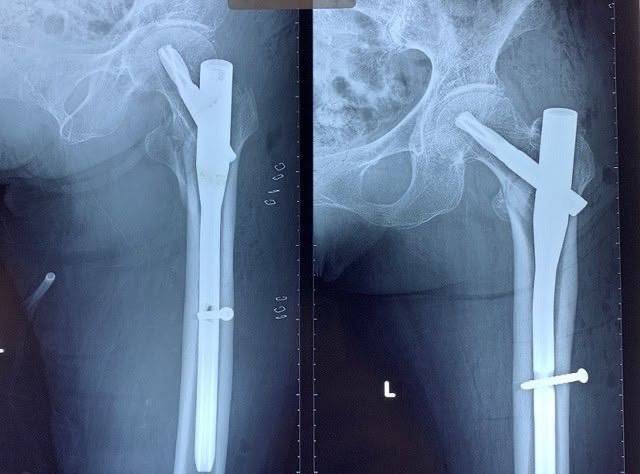

4.2. Điều trị phẫu thuật: Nếu không được điều trị phẫu thuật kịp thời bệnh nhân sẽ có những biến chứng nặng nề như: viêm phổi, viêm đường tiết niệu, đặc biệt gây loét các điểm tỳ và bệnh nhân sẽ tử vong do những biến chứng đó. Có nhiều chỉ định phẫu thuật khác nhau được đặt ra cho gãy LMC ở người cao tuổi như kết hợp xương ( đóng đinh nội tủy, nẹp DHS …), thay khớp háng. Mỗi phương án phẫu thuật có những ưu nhược điểm khác nhau. Đối với các loại gãy LMC di lệch phân độ A2.2 và A2.3 ( theo Muller), gãy xương kèm theo tình trạng thoái hóa khớp háng từ trước hoặc chất lượng xương yếu do loãng xương không đủ độ chắc để có thể giữ vững được các phương tiện kết hợp xương bên trong hoặc trong trường hợp đã điều trị thất bại đối với các phương pháp kết hợp xương trước đó thì chỉ định thay khớp háng nhân tạo cho bệnh nhân cũng là một giải pháp tốt.